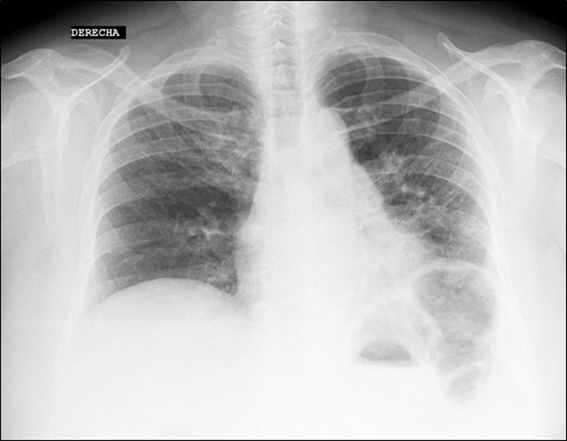

Además, paciente inicia disconfort postprandial, con sensación de llenura y disfagia. No hay variación en el apetito. La paciente es referida a un hospital nacional en Lima y se inicia estudio de la causa de la fibrosis pulmonar y dispepsia. En los exámenes auxiliares, en los resultados se ve dentro de la normalidad, excepto títulos elevados de Anticuerpos Antinucleares (ANA) en 1/5120 con patrón centromérico. Con dicho resultado se inició estudio de enfermedad autoinmune. El examen físico de abdomen no fue contributorio. Se realizó Tomografía Axial Computarizada (TAC) torácica (figura 2) donde se informa engrosamiento intersticial de tipo reticular a predominio subpleural posterobasal tipo panal de abeja en 2/3 inferiores pulmonares. Se realiza test de caminata, sin alteraciones.

Figura 2. Se pone en evidencia panalización progresiva a predominio subpleural, motivo del cansancio y fatiga en la paciente